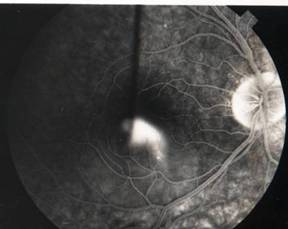

Smoke stack appearance

Ink blot appearance